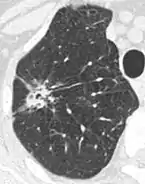

Air bronchograms is defined as a pattern of air-filled bronchi on a background of airless lung, and may be seen in both benign and malignant nodules, but certain patterns thereof may help in risk stratification.[9]